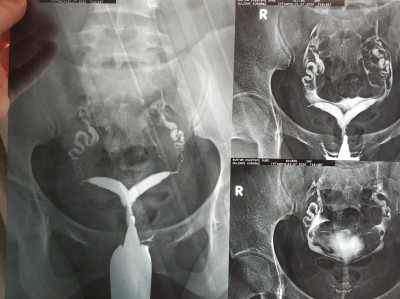

8 haftalık gebeyim kan kan ve geçen hafta kan uyuşmazlığı iğnesi yapıldı bu ikinci gebeliğim birincisi kalp atışı olmadıgı için 6. haftada ilaçlı düşük yapıldı bugün biranda su gibi kasn gelmeye başladı acile geldik muayene yapıldı kalp atışı var iğne yaptılar serum takıldı rahimde perde var ama doktorlar operasyondan önce denememizi söylediler o yüzden bunları yasıyorum Rabbim hayırlısını versin insallah ama çok yorucu

Gebelik haftası 8